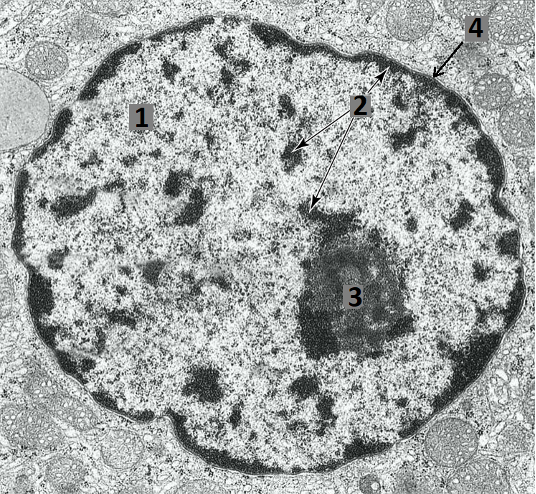

Pavadinkite elektronogramoje skaičiais pažymėtas struktūras:

0%

100%